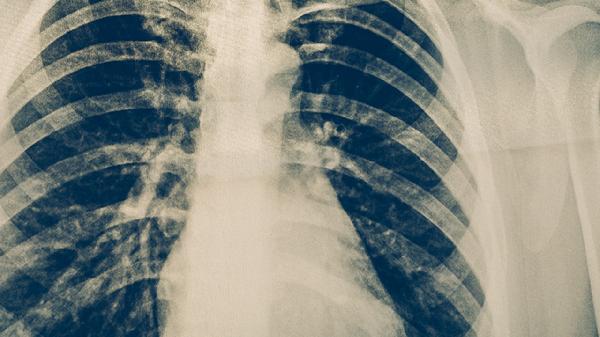

肺結(jié)核主要由結(jié)核分枝桿菌感染引起,常見原因有與肺結(jié)核患者密切接觸、免疫力低下、長期營養(yǎng)不良、居住環(huán)境擁擠潮濕以及合并糖尿病等慢性疾病。肺結(jié)核是一種慢性傳染病,主要通過呼吸道飛沫傳播,當(dāng)人體免疫力下降時(shí),結(jié)核分枝桿菌可能侵入肺部并繁殖,導(dǎo)致肺部組織發(fā)生炎癥反應(yīng)和壞死,形成結(jié)核結(jié)節(jié)。